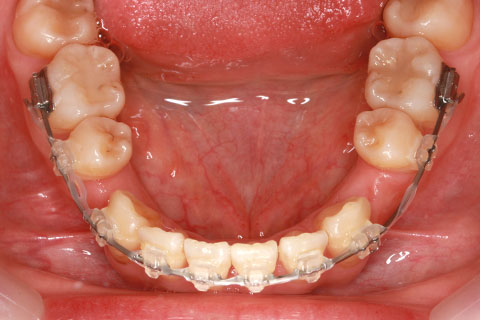

症例

治療前

治療中

治療後

- 年齢・性別

- 30歳女性

- 治療期間

- 3年0ヶ月

- 抜歯

- 上下左右4番抜歯

- 治療費

- 110万円

- 備考

- マルチブラケットを用いた矯正治療

- 治療内容

- 上下顎前突を4本抜歯にて矯正治療

- 施術の副作用(リスク)

- 表側矯正と比較して、歯根の角度を確立する「トルク」の力がかかりにくい。